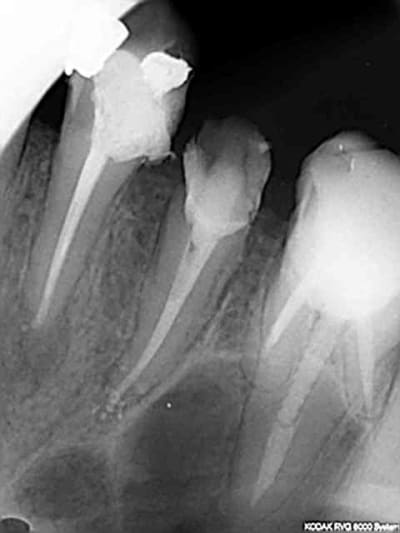

Endo 16 + sc 33. Costeaude la racine DV.

Capture d e cran 2015 07 30 15.33 - Eugenol

Ca m'arrive de foirer mais rarement, ici racine distale de 16 manque 2 mm. je n'essaie pas de forcer outre mesure et d'arriver à tout prix à l'apex.

Capture d e cran 2015 07 30 16.30 - Eugenol